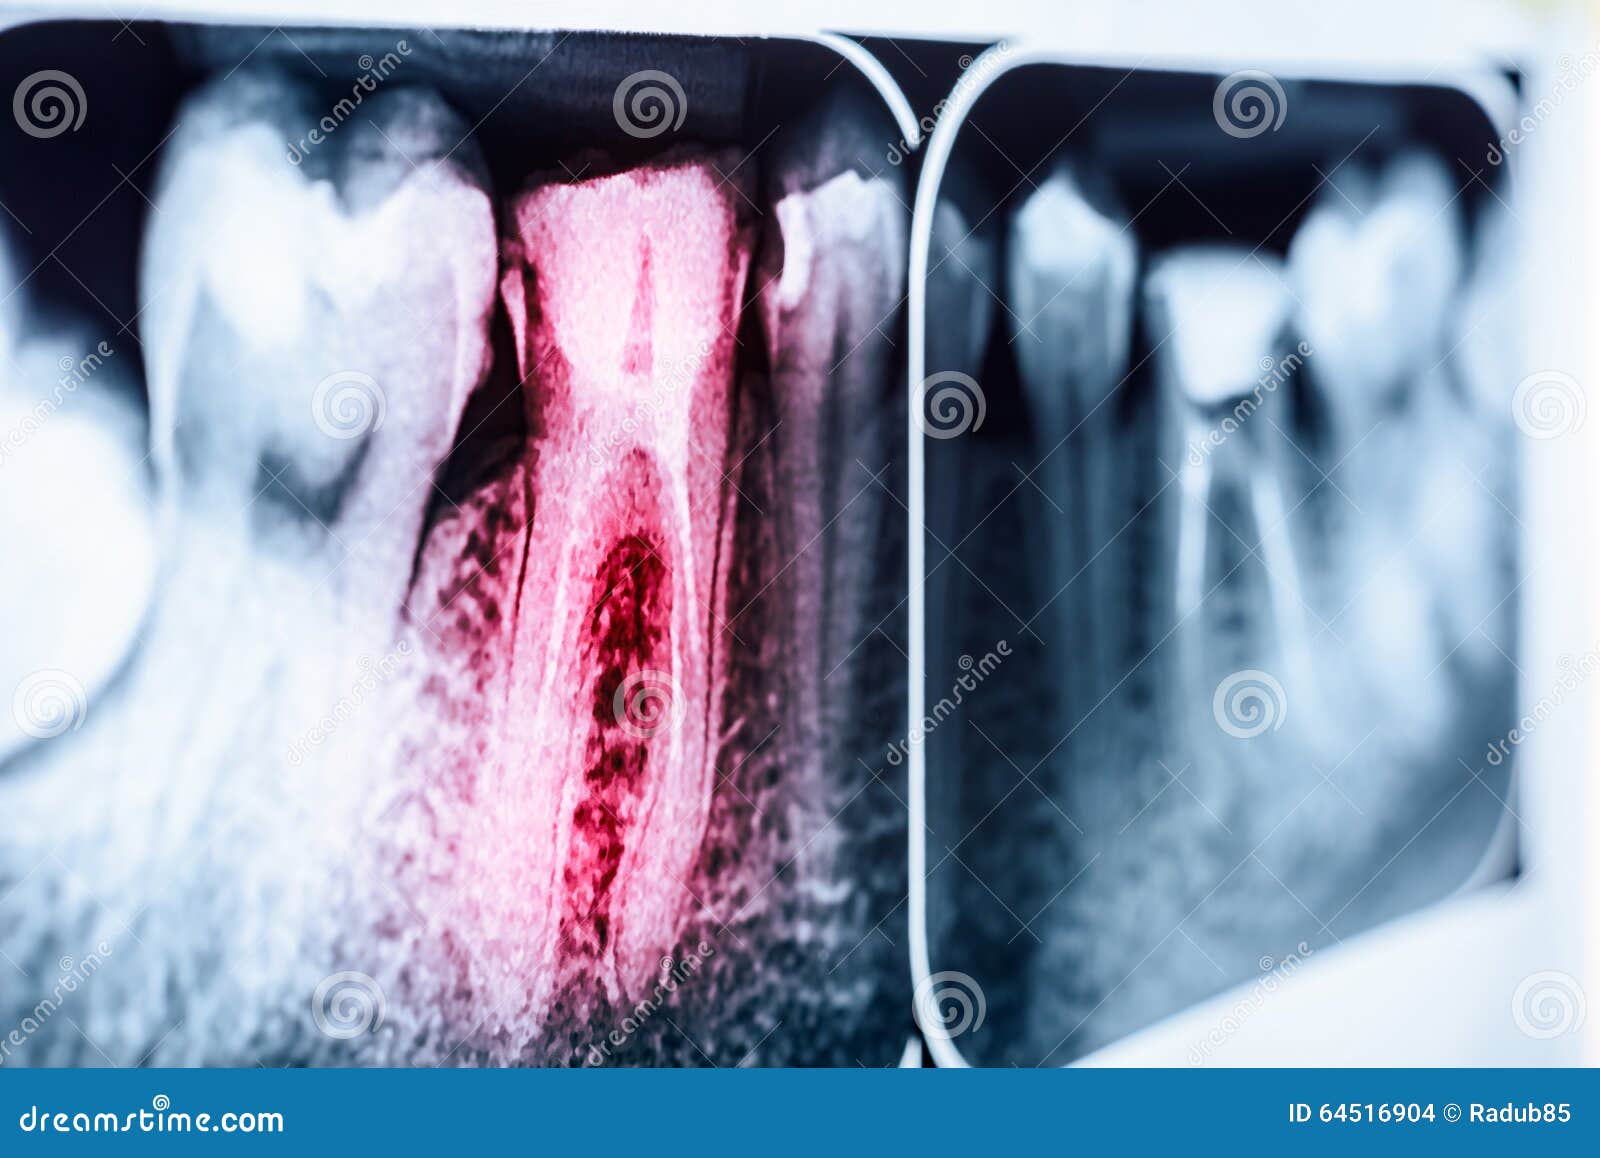

Pain of Tooth Decay on XRay Stock Photo Image of film, mouth 64516904 Tooth Pain After X Ray The second most common cause is a cracked tooth. The most common cause of tooth pain is infection. But there are lots of possible reasons why this is happening, from referred pain to hidden problems deep inside your tooth. Where the pain could be coming from. Sometimes, tooth pain can occur due to sensitivity caused by worn enamel or exposed. Tooth Pain After X Ray.

From keysdentalspecialists.com